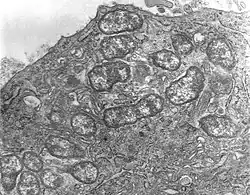

Orientia tsutsugamushi

Scrub typhus or bush typhus is a form of typhus caused by the intracellular parasite Orientia tsutsugamushi, a Gram-negative α-proteobacterium of family Rickettsiaceae first isolated and identified in 1930 in Japan.[2][3]

Although the disease is similar in presentation to other forms of typhus, its pathogen is no longer included in genus Rickettsia with the typhus bacteria proper, but in Orientia. The disease is thus frequently classified separately from the other typhi.